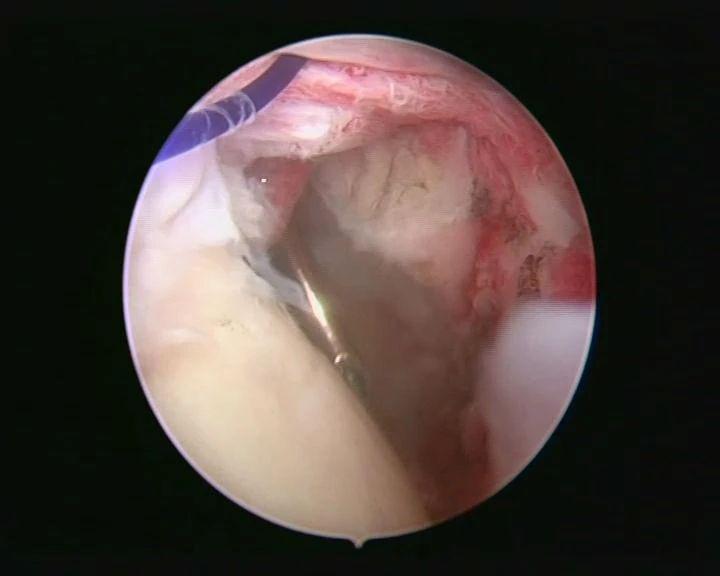

治疗团队完善相关检查后,决定为患者实施巨大肩袖撕裂的全关节镜下修补缝合术。传统的肩关节手术创伤大、出血多、探查不全面、术后恢复慢、有较大手术瘢痕等,通过关节镜对关节内的结构和病变直接观察和治疗,准确性高且损伤性较低。术中治疗团队应用关节镜下微创技术,根据术中实际情况,精准植入缝合锚钉,将撕裂的肩袖缝合回原本的位置,恢复其原本具有的功能。术后患者患肢的活动受限症状立即得到了缓解,患者对治疗效果非常满意,目前恢复良好,右肩活动及功能已有明显改善。